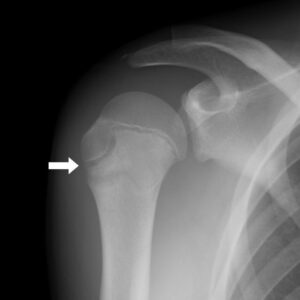

上腕骨骨端線障害(リトルリーグショルダー)

成長軟骨部分に負荷がかかり、骨端線が離開すると説明される状態。

画像引用元:上腕骨近位骨端線損傷 | さいたま整形外科クリニック